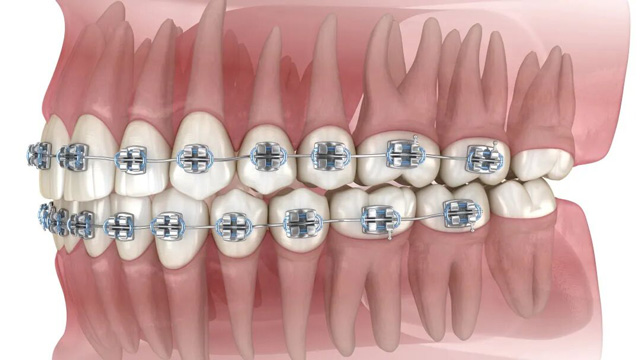

02智齿阻挡正畸牙齿移动

正畸治疗中,医生会根据诊疗方案,让牙齿沿着预设轨迹移动(比如前牙内收、后牙调整咬合等)。比如需要内收前牙改善凸嘴时,智齿的存在会“顶住”后牙,导致牙齿无法顺利移动到理想位置。这种情况,可能需要拔除智齿来为排齐牙齿提供必要的空间。